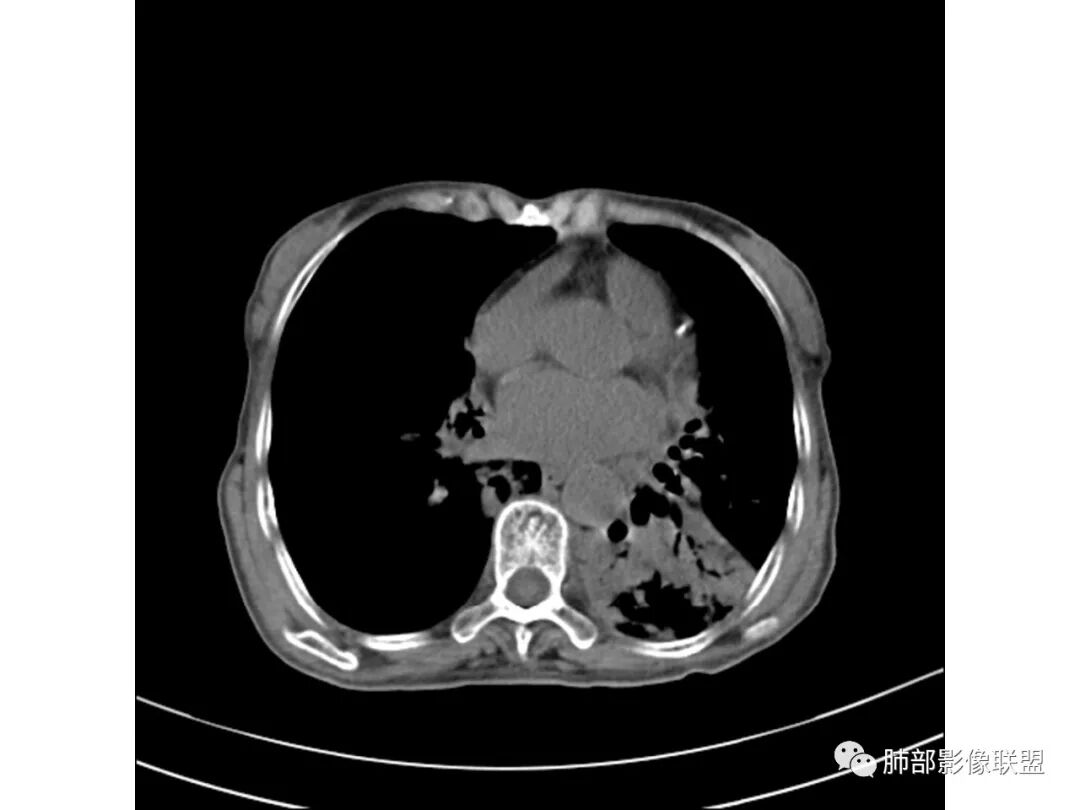

大家看看这支气管

这些支气管扩张

支气管有扩张

支气管扩张、扭曲成团,附近钙化灶

肿瘤会这样吗?

这例左下叶的体积是整体缩小的,左下叶的支气管主干稍微小一点点,然后左上叶的下舌段也有类似的病灶,然后我们看到一团乱的支气管扩张,但它有特点,边缘凹凸不平。那什么样的支气管扩张边缘会如此凹凸不平呢,等我截个图:

看最后一幅图,上面这个支气管,有可能是淋巴瘤,为什么?他的支气管稍扩张,直达远端、实变。

首先这幅图支气管很多地方是扭曲的,远端扩张的特别厉害。如果是肿瘤,首先考虑淋巴瘤,因为支气管可直达远端,稍扩张,但是它的前提是周围要实性占位的,而且它不会这样扭曲变形。我们看这个病例的支气管扩张,它支气管扩张占大部分区域,中间稍有些实性的结构,这就不符合了。这幅图你会发现所有支气管都是扩张的,实性部分偏少,外围胸水。所以我更倾向慢性炎性病变,能够引起支气管扩张的炎性病变有哪些?结核?NTM?支扩伴感染?大方向是慢性炎性病变。这些左下肺播散出来的病灶,咳中等量黄浓痰,我考虑还可能合并细菌感染。